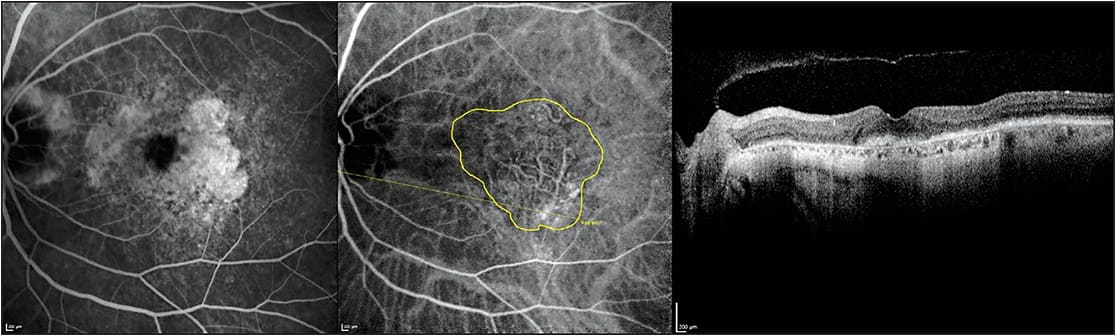

Figure 1. Fluorescein angiography (left), indocyanine green angiography (middle), and optical coherence tomography (right) of a 77-year-old woman with neovascular age-related macular degeneration undergoing bevacizumab therapy using a treat-and-extend protocol. The patient was imaged during the follow-up examination following a successful treatment extension to an eight-week interval. Her Snellen visual acuity was 20/30. Notice the absence of retinal fluid on optical coherence tomography. The choroidal neovascularization is encircled in yellow on indocyanine green angiography and measures 5.79 mm2. Prominent geographic atrophy is evident by fluorescein angiography and optical coherence tomography, but the choroidal neovascularization is indistinct on these systems. The patient was treated with bevacizumab during this follow-up and extended out to a 10-week interval.